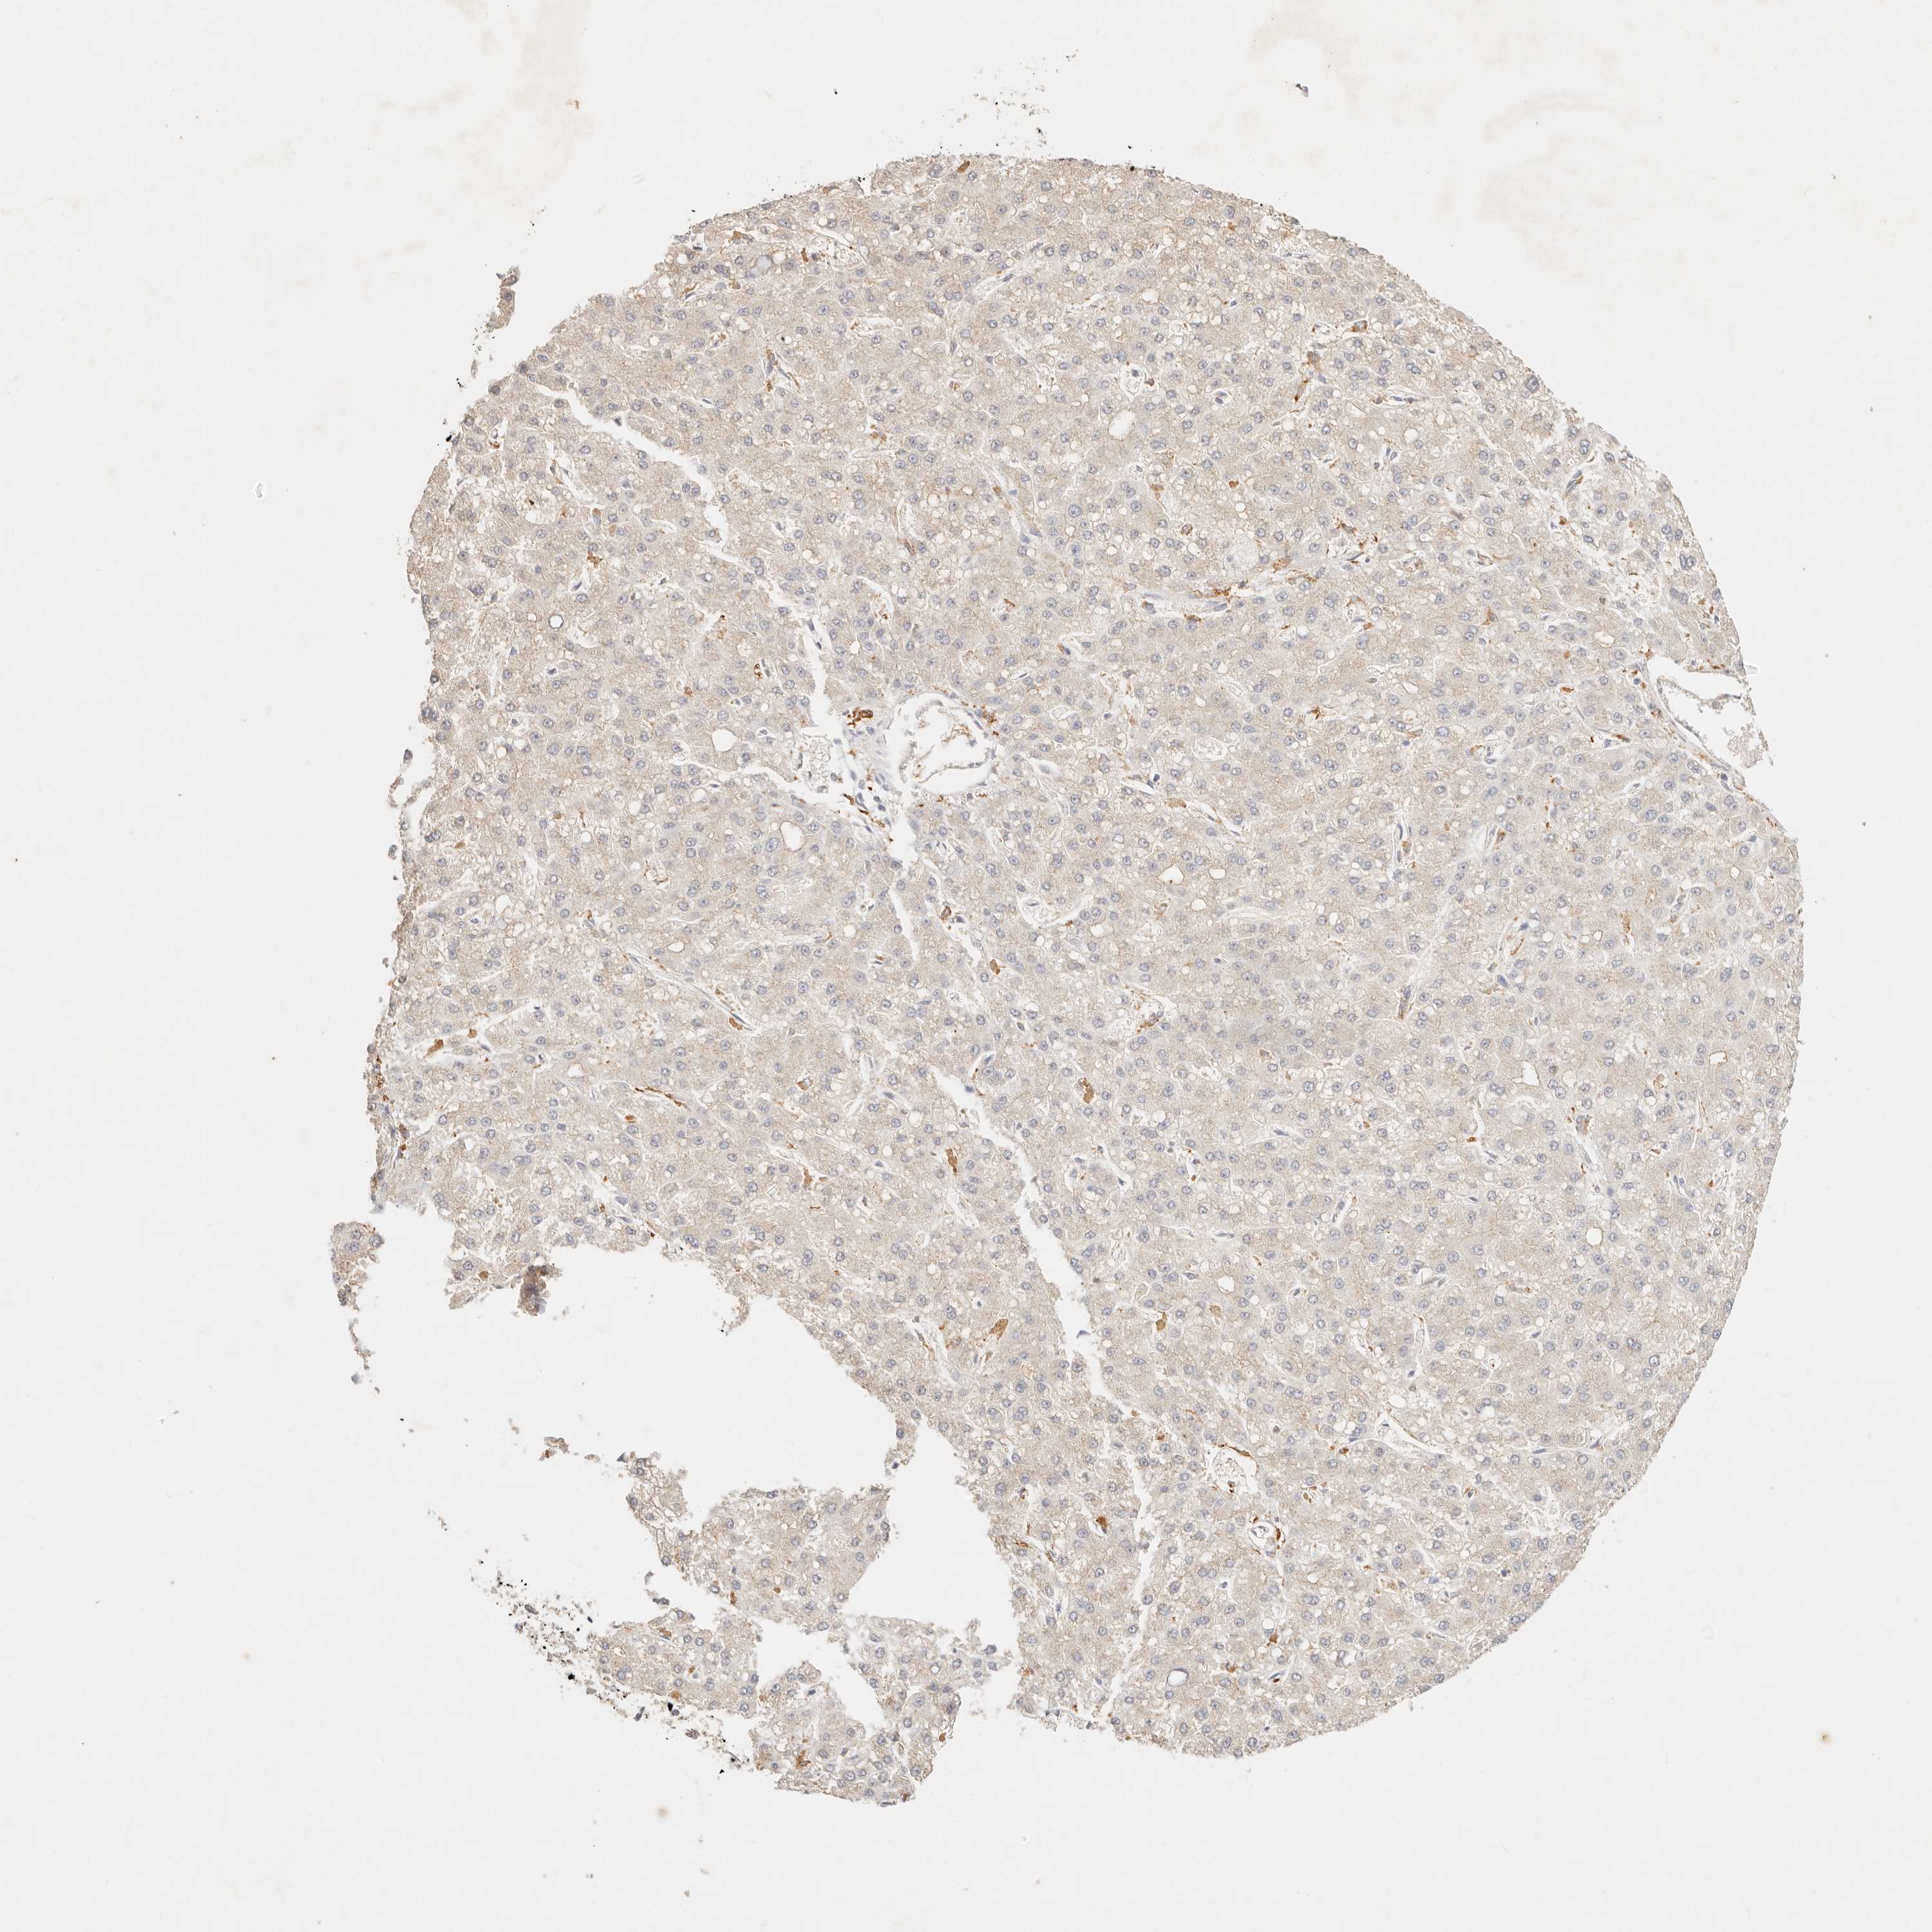

LIVER CANCER - Protein expressioni

A mouse-over function shows sample information and annotation data. Click on an image to view it in a full screen mode. Samples can be filtered based on level of antibody staining by selecting one or several of the following categories: high, medium, low and not detected. The assay and annotation is described here.

Antibody stainingi

Antibody staining in the annotated cell types in the current human tissue is reported as not detected, low, medium, or high, based on conventional immunohistochemistry profiling in selected tissues. This score is based on the combination of the staining intensity and fraction of stained cells.

Each image is clickable and will lead to virtual microscopy that enables deeper exploration of all samples and also displays staining intensity scores, fraction scores and subcellular localization as well as patient and tissue information for each sample.

Antibody HPA028587

Staining

High

Medium

Low

Not detected

Intensity

Strong

Moderate

Weak

Negative

Quantity

>75%

75%-25%

<25%

None

Location

Nuclear

Cytoplasmic/membranous

Cytoplasmic/membranous,nuclear

Cholangiocarcinoma

Carcinoma, Hepatocellular, NOS